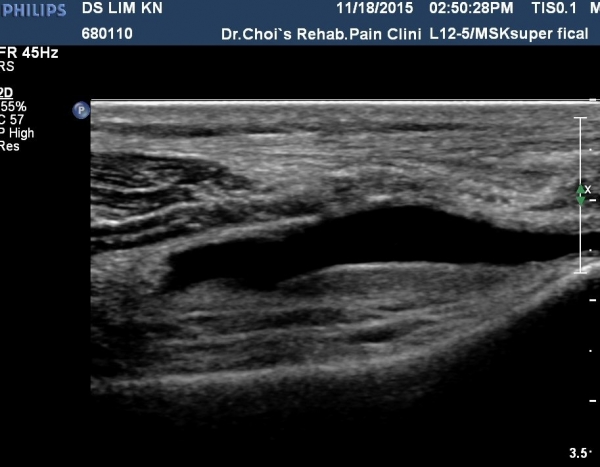

ÃÊÀ½ÆÄ °Ë»ç

¹«¸­ ¿ÜÃø Á¾´Ü¸é°Ë»ç¿¡¼­ °üÀý³» ¼ö¾×Àú·ù°¡ °üÂûµÊ(»çÁø 1, 2).